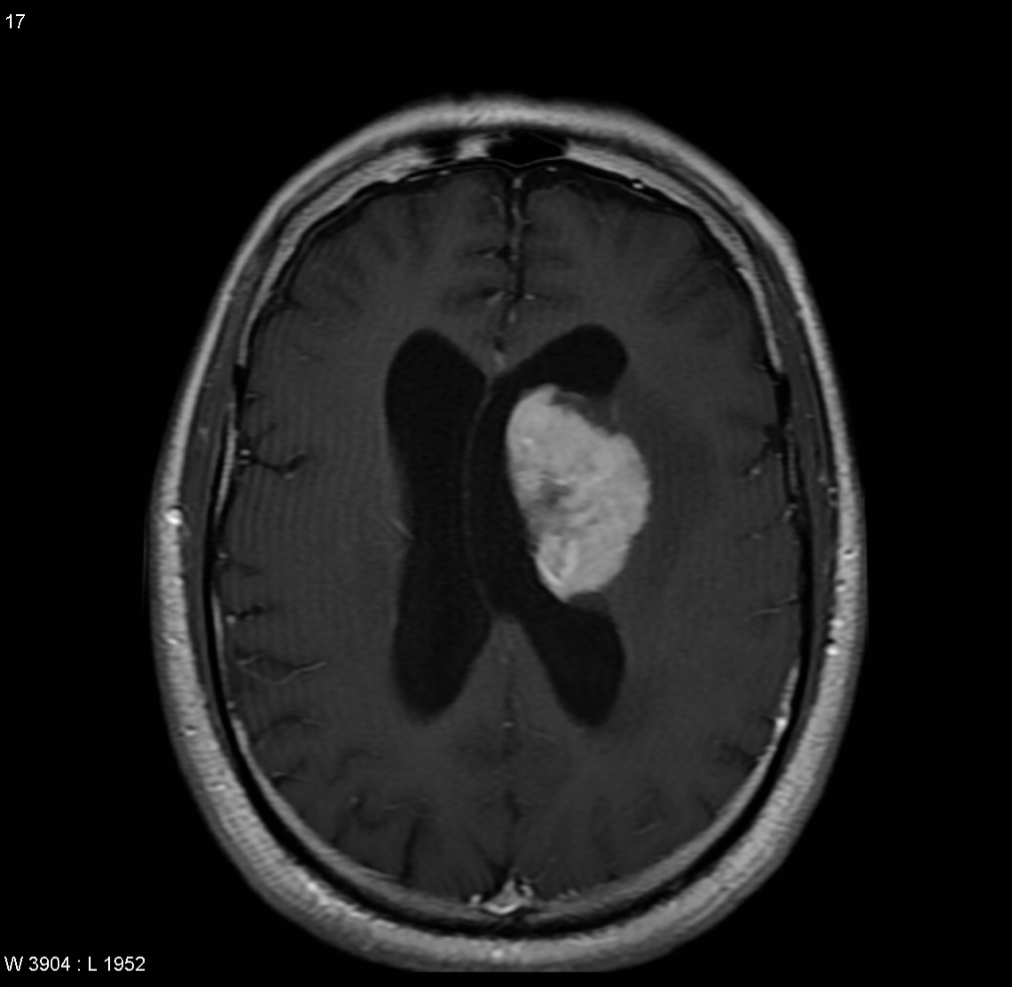

What two CNS mass lesions are associated with HIV/AIDS

1) Toxoplasmosis (multiple ring-enhancing lesions w/ edema)

2) CNS lymphoma (hyperdense, round enhancing lesions)